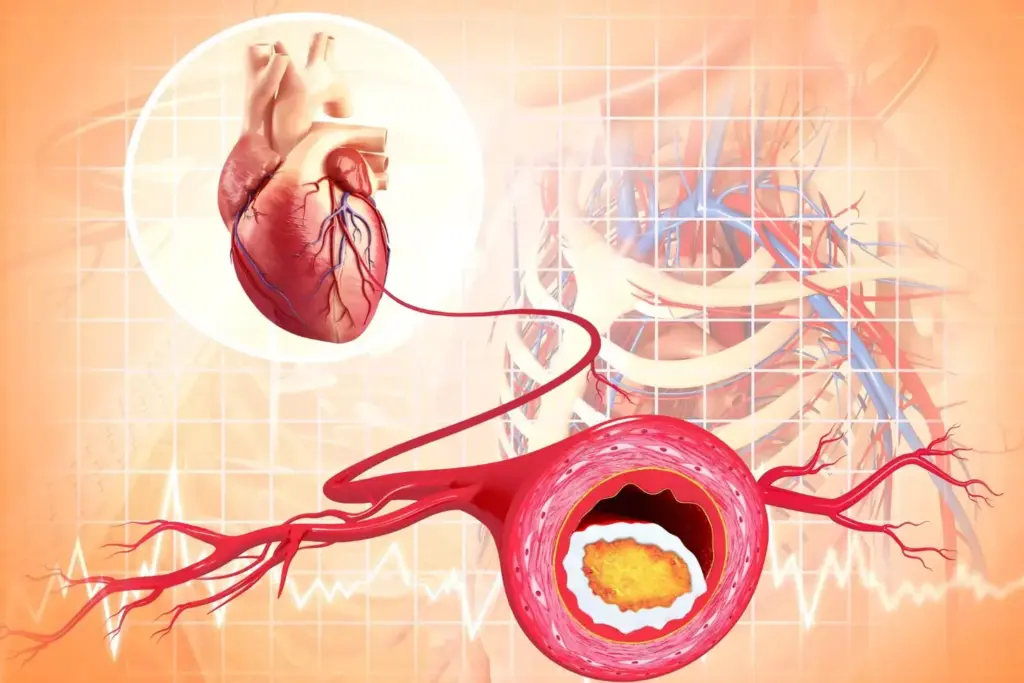

The Mechanism Behind Heart Attacks

The mechanism behind heart attacks involves a complex interplay of factors that ultimately lead to the obstruction of blood flow to the heart muscle. Coronary artery disease is the primary culprit, where plaque buildup in the arteries leads to their narrowing or complete blockage.

“The most common cause of myocardial infarction is the rupture of an atherosclerotic plaque, leading to acute thrombosis and occlusion of a coronary artery,” as emphasized by cardiovascular research.

Coronary Artery Disease as the Primary Cause

Coronary artery disease (CAD) is the underlying cause of most myocardial infarctions. CAD involves the narrowing or blockage of the coronary arteries due to atherosclerosis, which is the buildup of plaque composed of fat, cholesterol, and other substances.

The progression of CAD can lead to reduced blood flow to the heart, causing angina or, if severe, a myocardial infarction. Understanding the risk factors for CAD is crucial for prevention, as it allows for early intervention and management.